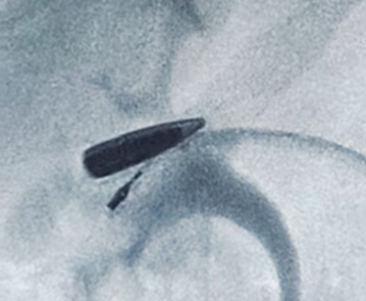

Пуля мигрировала по венозной системе.

В НИИ скорой помощи им. Склифосовского поступил пациент с огнестрельным ранением над ключицей. При обследовании выяснилось, что пуля, попавшая в шею, мигрировала по венозной системе и остановилась в правой почечной вене. Врачи столкнулись с таким случаем на практике впервые.

Для спасения жизни пациента была оперативно собрана бригада сосудистых и рентген-эндоваскулярных хирургов. Перед врачами стояла сложнейшая задача: выделить почечную вену и артерию, пережать сосуды почки и извлечь пулю, не допустив при этом необратимых повреждений органа.

Операция по извлечению пули прошла успешно и заняла рекордно короткое время – всего 6 минут. Это позволило избежать отмирания почки. Сейчас пациент чувствует себя хорошо и уже выписан из больницы.